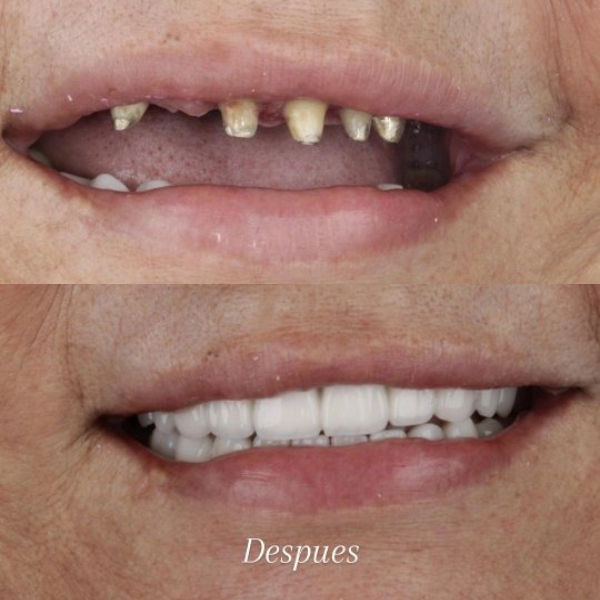

Before and After Gallery